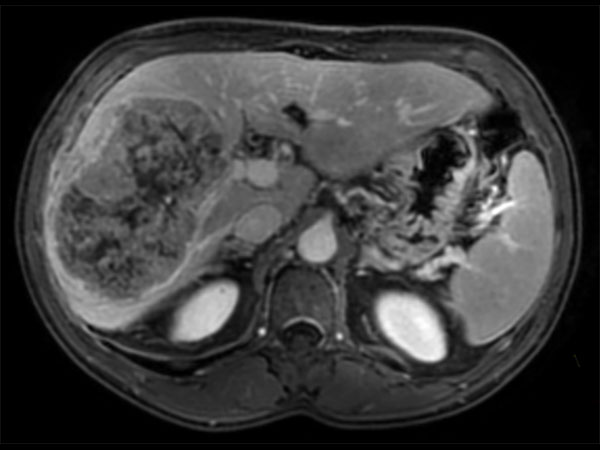

62 year old patient with huge, non-cirrhotic liver tumor. Question is if the portal vein is closed or not which has a direct influence on treatment options. Portal vein turned out to be open and patient was referred for embolization. No other tumors / lesions were found.

Axial T2w SPAIR